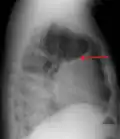

A pleural effusion appears as an area of whiteness on a standard posteroanterior chest X-ray.[15] Normally, the space between the visceral pleura and the parietal pleura cannot be seen. A pleural effusion infiltrates the space between these layers. Because the pleural effusion has a density similar to water, it can be seen on radiographs. Since the effusion has greater density than the rest of the lung, it gravitates towards the lower portions of the pleural cavity. The pleural effusion behaves according to basic fluid dynamics, conforming to the shape of pleural space, which is determined by the lung and chest wall. If the pleural space contains both air and fluid, then an air-fluid level that is horizontal will be present, instead of conforming to the lung space.[16] Chest radiographs in the lateral decubitus position (with the patient lying on the side of the pleural effusion) are more sensitive and can detect as little as 50 mL of fluid. Between 250 and 600mL of fluid must be present before upright chest X-rays can detect a pleural effusion (e.g., blunted costophrenic angles).[17]

A pleural effusion as seen on lateral upright chest x-ray -

Pleural effusion as seen behind the heart.[20]